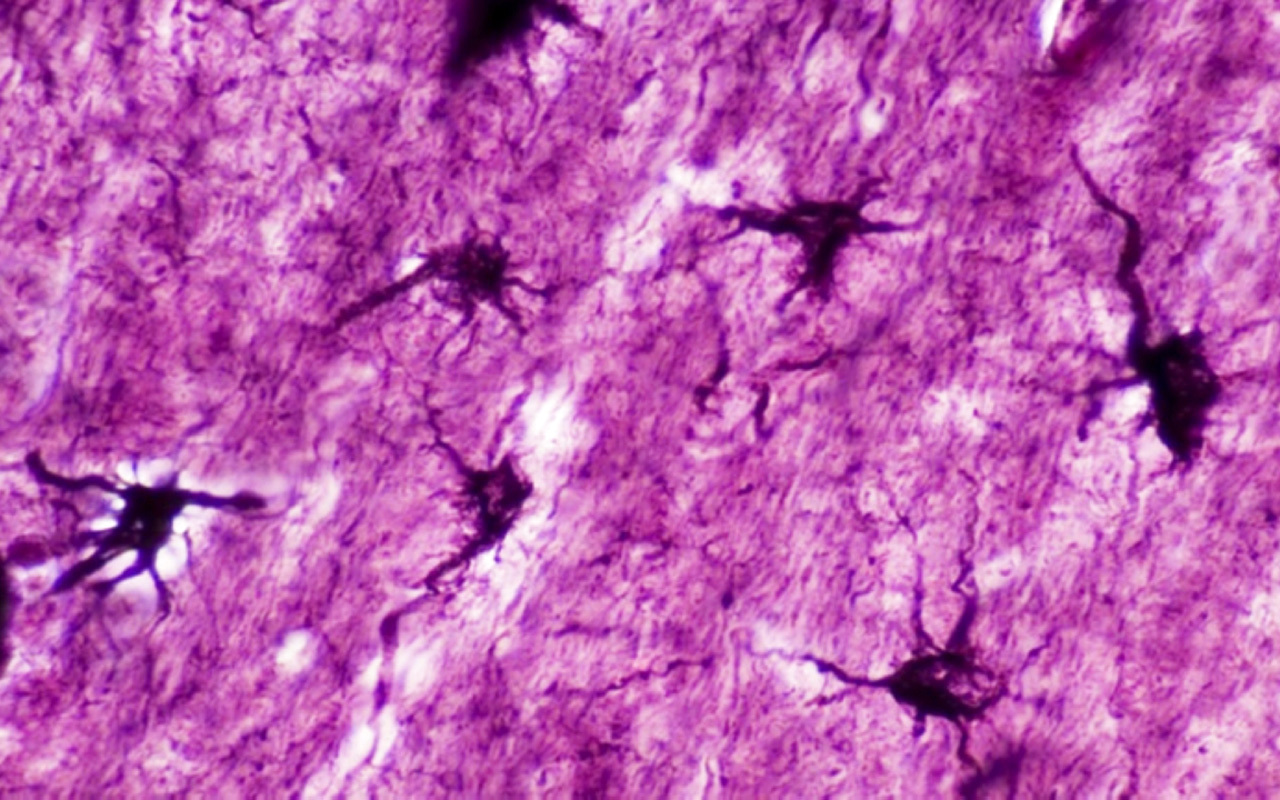

وكشفت الدراسة أن ما يعرف باسم الخلايا النجمية (الخلايا الداعمة)، تكون وفيرة في الدماغ وتلتف حول الوصلات العصبية مثل «الغراء». وظهرت أدلة مهمة، تؤكد أن الخلايا النجمية قد تساهم في «إطلاق» الخلايا العصبية عن طريق إفراز الغلوتامات، الناقل العصبي الرئيسي في الدماغ.

وبهذا الصدد، عثر باحثون من مؤسسات مختلفة في المملكة المتحدة وأوروبا، على خلية هجينة جذرية في أدمغة الفئران.

ووجد الباحثون أن الخلايا المتخصصة تطلق الغلوتامات في نقاط ساخنة دقيقة تشبه المشبك العصبي، الذي يشمل المساحة التي تتواصل فيها خليتين عصبيتين عادة عن طريق إطلاق الغلوتامات.